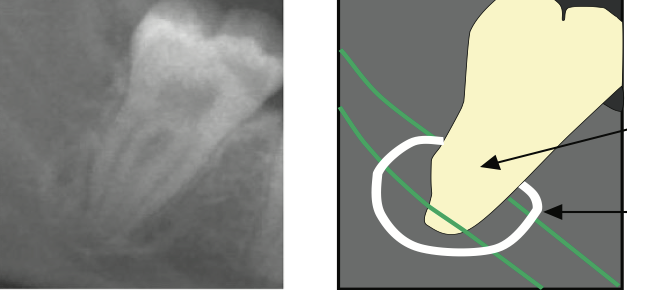

what is this?

Interruption of the white lines/lamina dura of the canal